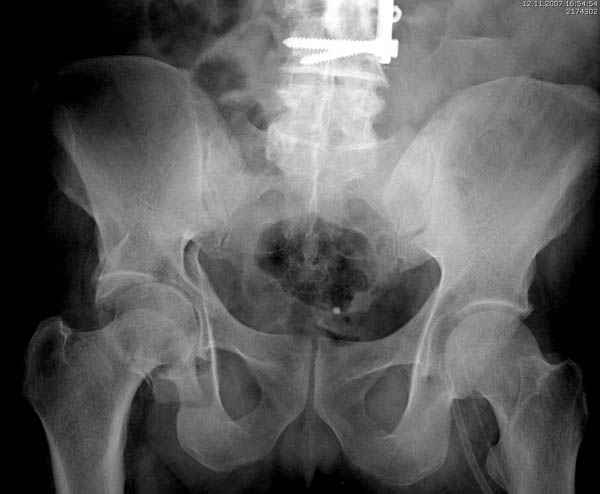

Дополнительно имеется перелом ацетабулума: задняя

колонна с полупоперечным переломом, и переломы костей лица.

На седьмой день зафиксирован перелом ацетабулума через задний доступ. Перед операцией для профилактики DVT, IVC фильтер, также получает Lovenox.

Извиняюсь за качества снимков, обычный больной в 300 фунтов, портативным ренген аппаратом не пробить.